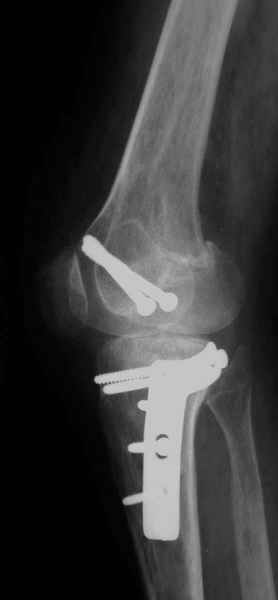

Тут ситуация совсем другая. Деформация не около-, а самая что ни на есть внутрисуставная. Покорректировать внешний вид конечности путем остеотомии дистального отдела бедра и high tibia (плюс или минус клин, одномоментно-постепенно, аппарат-пластина-стержень - дело третье) не сильно сложно, но это не решение проблемы. У больной, по

сути отсуствует латеральный отдел коленного сустава, что требует костно-пластических вмешательств непосредственно на артикулирующих

поверхностях.

Может быть, целесообразней сразу протез, чем тот же протез, но после сложных, но сомнительно результативных операций типа замещения алломыщелком, моделирующих резекций и т.п.? Ну и в любом случае движения лучше бы разработать получше до любой операции.

Деформация не около-, а самая что ни на есть внутрисуставная.

-Деформация оси сустава может быть варусной или вальгусной, причины - структурные изменения в латеральном -или медиальном отделе сустава (переломы, патология зон роста, дисплазии, дегенеративные процессы) результат лечения внутри- или внесуставного перелома и восстановление оси обуславливается анатомичностью репозиции и адекватностью фиксации. Нередко в запущенных -неправильно срасшихся unicompartmental внутрисуставных переломах восстановление оси и опороспособности достигается периартикулярными

остеотомиями...

- *как разбитую чашку не клей - все равно новой она уже не станет*, - поэтому при подтверждении некроза мыщелка бедра в сочетании с деструкцией тибиального плато, артропластика остаётся единственной альтернативой для восстановления функции и опорности ноги.